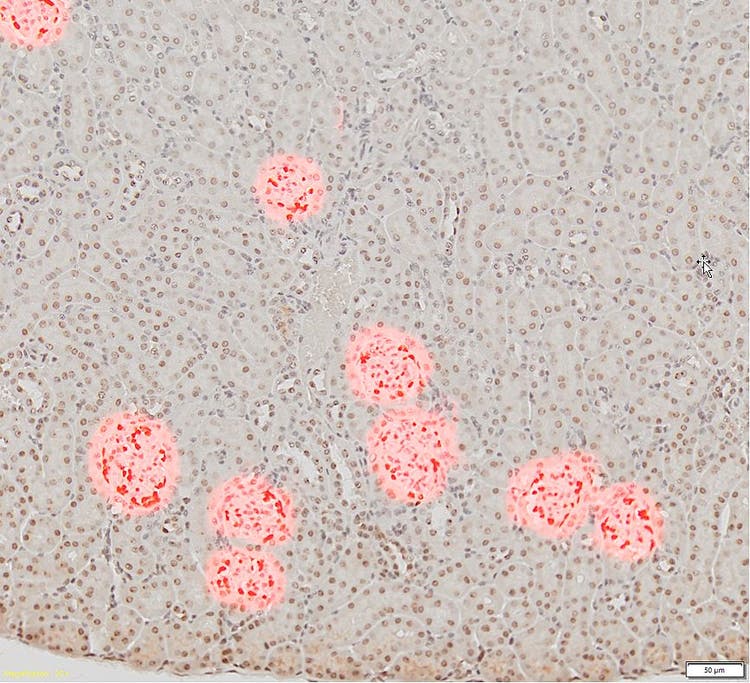

腎組織切片のスライド。20倍で糸球体をこげ茶色で染色したもの(左)と、10倍で従来のしきい値法に基づく検出を示した(赤色)もの(右)。糸球体細胞を他の組織細胞と区別できません。

画像提供:Zhenhua Miao, Principal Scientist at ChemoCentryx, Inc. Mountain View, CA (USA)

スキャン画像内でこれらの構造を解析する場合、研究者は通常、手作業で糸球体を選択しますが、作業はとても時間がかかります。 さらに、しきい値に基づくアルゴリズムなど、従来の自動セグメンテーション方法では、上に示したように糸球体のみを検出できません。